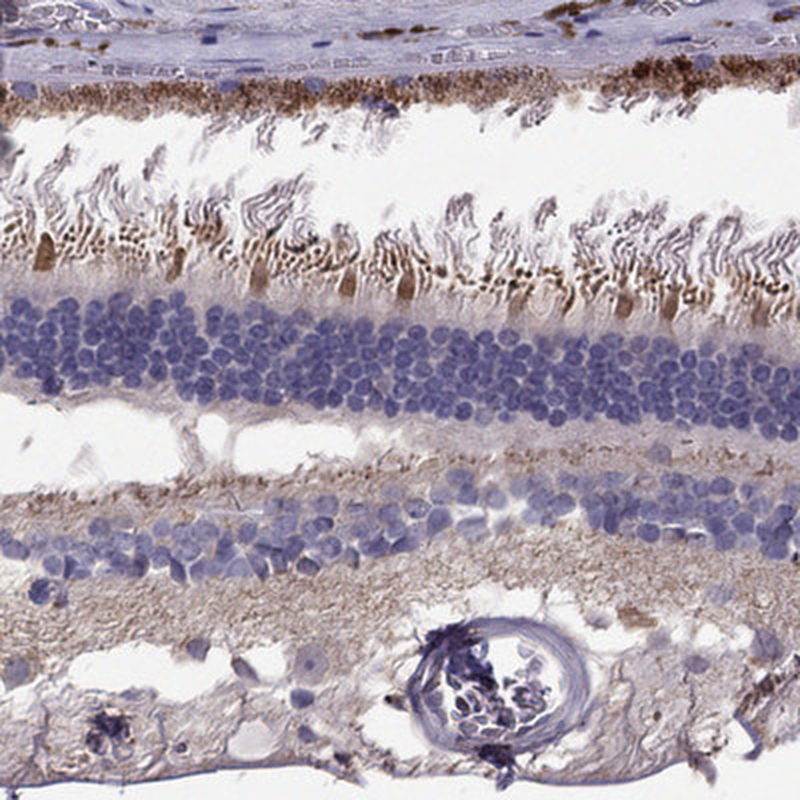

Immunohistochemical staining of human retina shows strong cytoplasmic positivity in photoreceptor segments